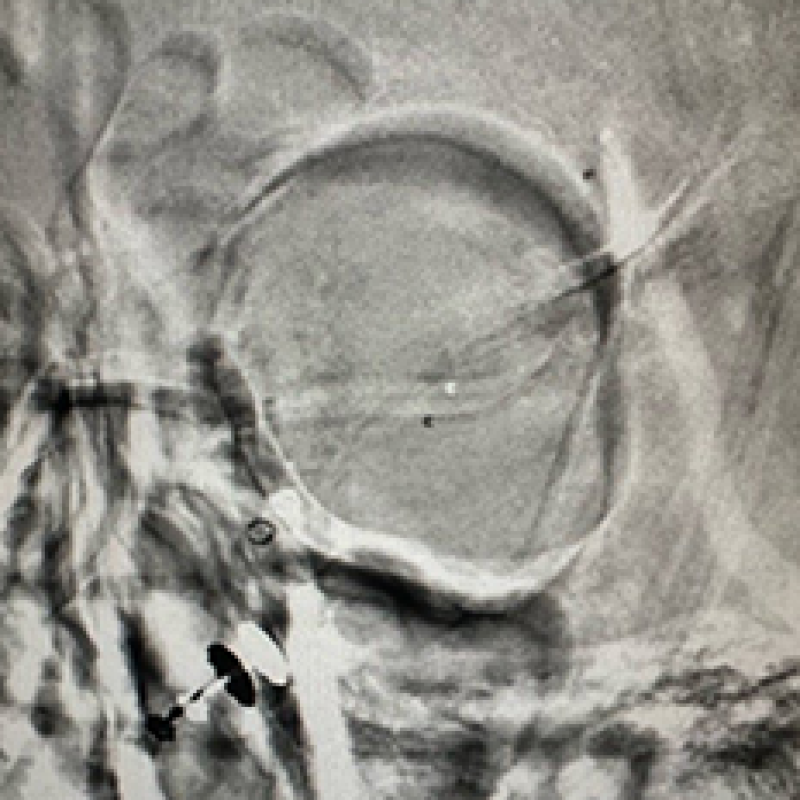

We provide devices and treatment of complex brain aneurysms and vascular malformations free of cost. These are some of the complex brain aneurysm we have recently treated in Pakistan. Devices and catheters used for all procedures were provided by Pakistan Stroke Initiative, and in some cases charges for hospitalization as well.

Although we typically don’t take photos of our patients and their families, many of those we have treated have made special requests for it. Visiting physicians from abroad have consistently been impressed by the gratitude and appreciation shown by our patients and their families for the care they receive.

All of these photos have been shared with the permission of the patients and their families.